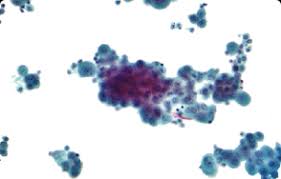

cytology description ===== disadvantage of cytology cannot assess invasion. Cell type of malignant mesothelioma histology When irritated or injured, the mesothelial lining of the peritoneal cavity can show focal or diffuse hyperplasia. If this component is > Ascoli v, minelli g, cozzi i, romeo e, carnovale scalzo c, ancona l, et al. Biphasic mesothelioma, epithelioid mesothelioma, desmoplastic mesothelioma, sarcomatoid mesothelioma. Implications for diagnosis and histogenesis. In a 2019 case study, the patient claimed to have lung cancer, but proper pathology scans showed mesothelioma cancer cells, not lung cancer cells. It should not be confused with benign multicystic mesothelioma and benign papillary. cytology was correct in 87 of 93 cases (diagnostic accuracy, 94 percent). Wdpm is usually benign but can turn into malignant mesothelioma. This condition often accompanies certain specific underlying medical conditions. This may lead to a stronger prediction.

In pleural cytology specimens exhibiting markedly reactive mesothelial cells, for which the diagnosis of diffuse malignant mesothelioma (dmm) is being entertained, it is almost always impossible to definitively determine whether such cytological findings represent markedly reactive mesothelial cells or dmm cells. mesothelioma cytology, or mesothelioma cytopathology, is the study of cells for the presence of mesothelioma. The diagnosis of desmoplastic malignant mesothelioma and its distinction from fibrous pleurisy: Some of the situations where mesothelial hyperplasia may be encountered include: Malignant mesothelioma, also mesothelioma, is a form of cancer. pathology uses cellular inspection to differentiate cancerous cells from healthy tissue. mesothelioma vs adenocarcinoma pathology outlines. It should not be confused with benign multicystic mesothelioma and benign papillary. Refers to the study of cell structure and how cells function. Ascoli v, minelli g, cozzi i, romeo e, carnovale scalzo c, ancona l, et al. Specimen types include exfoliated cervical cytology (pap tests), urine, body cavity fluids (pleural, pericardial, and peritoneal), cerebrospinal fluid, and fine needle aspirations from any body site, among others (see detail articles section).these are often collected by minimally invasive means. To file a mesothelioma lawsuit, you have to have a diagnosis of any mesothelioma type: Epithelioid mesothelioma is the most common cell type of mesothelioma cancer.